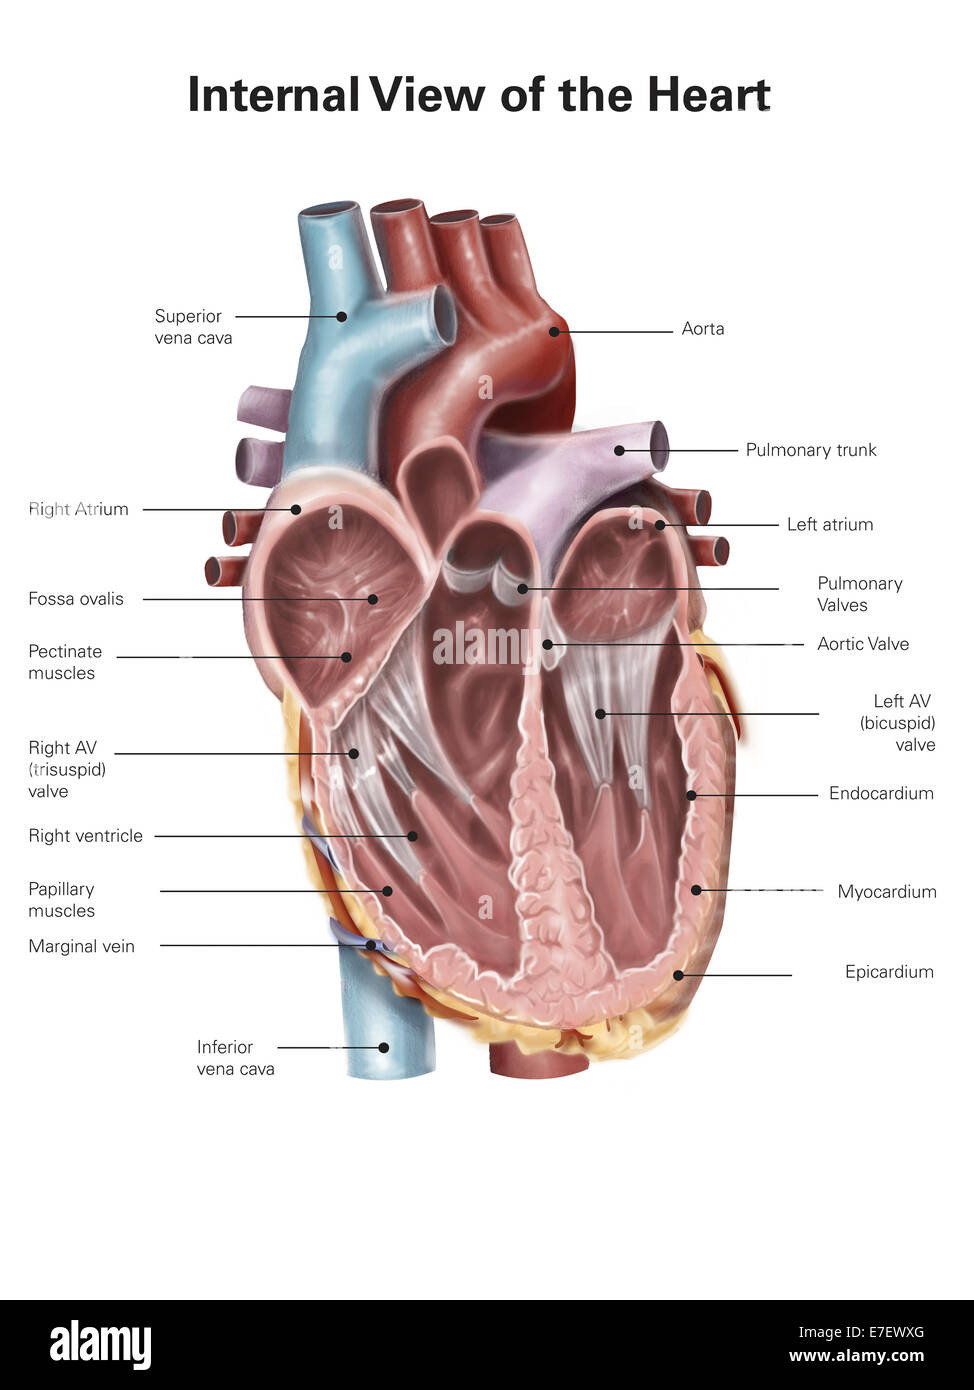

Internal view of the human heart. Stock Photohttps://www.alamy.com/image-license-details/?v=1https://www.alamy.com/stock-photo-internal-view-of-the-human-heart-73471736.html

Internal view of the human heart. Stock Photohttps://www.alamy.com/image-license-details/?v=1https://www.alamy.com/stock-photo-internal-view-of-the-human-heart-73471736.htmlRFE7EWXG–Internal view of the human heart.